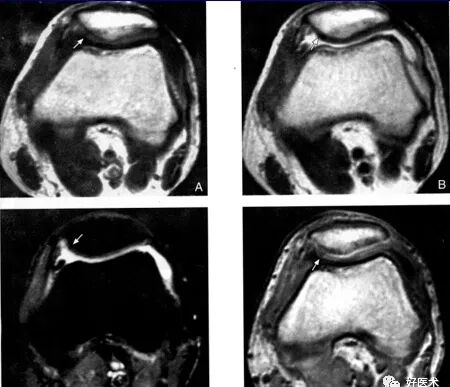

髌骨软骨软化症MRI表现:

Ⅰ级:

A:SE序列T1加权像

B:SE序列T2加权像

C:STIR像

D:PGE序列T1加权像

Ⅱ级: